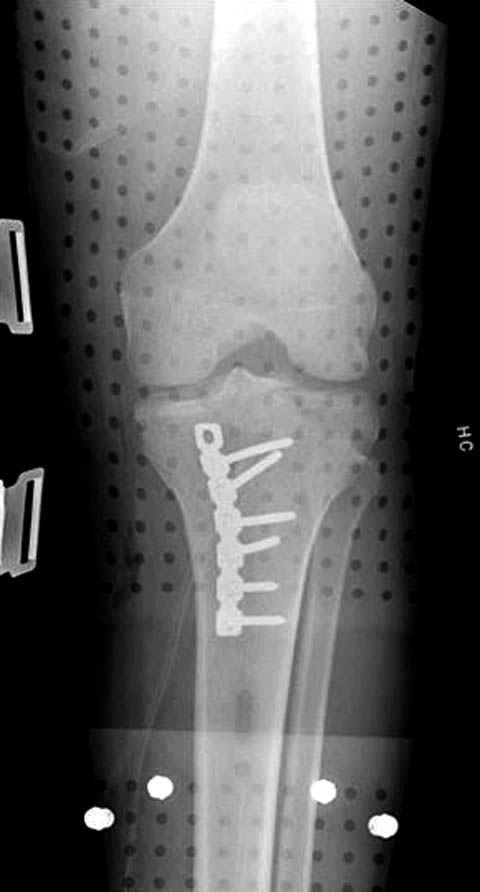

Трудно поверить, что разрекламированная Ортопедическая школа Восточной Украины позволяет такие странные снимки? На прямом снимке сохранен общий контур плато, но не известна судьба импрессии суставной поверхности. На полубоковой?, оставлен без репозиции задне-медиальный отдел, и навряд ли после такой фиксации можно удовлетвориться результатом.

Представленные снимки не информативны, нужны отдельные качественные снимки коленного сустава и голени без ротации.